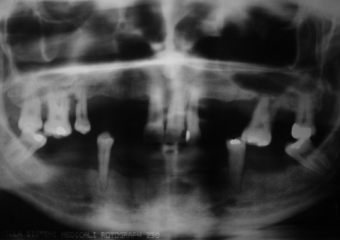

Raio X inicial